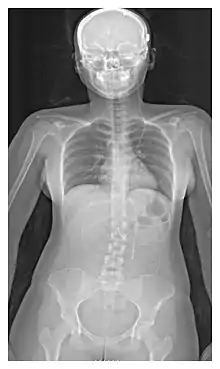

L'emplacement de la dérivation est déterminé par le neurochirurgien en fonction du type et de l'emplacement du blocage provoquant l'hydrocéphalie. Tous les ventricules cérébraux sont candidats à la dérivation. Le cathéter est le plus souvent placé dans l'abdomen, mais d'autres emplacements incluent le cœur et les poumons. les dérivations peuvent souvent porter le nom de la voie utilisée par le neurochirurgien. L'extrémité distale du cathéter peut être située dans à peu près n'importe quel tissu comportant suffisamment de cellules épithéliales pour absorber le LCR entrant. Ci-dessous quelques plans de routage courants pour les dérivations cérébrales :

| Dérivation ventriculo-péritonéal (Dérivation VP) | Cavité péritonéale |

| Dérivation ventriculo-auriculaire (Dérivation VA) | Oreillette droite du cœur |

| Dérivation ventriculo-pleural (Dérivation VPL) | Cavité pleurale |

| Dérivation ventriculo-cisternal (Dérivation VC) | Grande citerne |

| Dérivation ventriculo-sous-galéal (Dérivation SG) | Espace sous-galéal |

| Dérivation lombaire-péritonéal (Dérivation LP) | Cavité péritonéale |